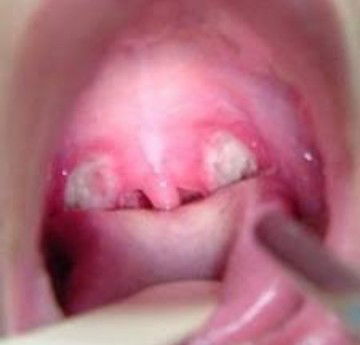

.saya kurang tau sih ya bund kalo di bayi,, tapi saya ngalamin sendiri pas covid, persis kaya gitu, gede nya juga kaya gitu... dan itu rasanya, uuuuggghhhhh sakit bgt, buat nelen pun susah... kaya sariawan gitu, tp di tenggorokan..

bukan bayi ku sih, tapi aku pernah ngalamin kaya gini, rasanya perih sakit kalo buat nelen, tenggorokan putih2 gini,mending ke dsa bun